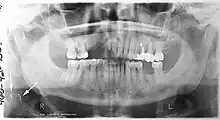

Panoramic radiograph

A dental panoramic radiograph, showing the maxilla and mandible, all the teeth including the "wisdom teeth," the frontal and maxillary sinuses, the nasal cavity and the temporomandibular joint and other near by head and neck anatomy. | |

A panoramic radiograph is a panoramic scanning dental X-ray of the upper and lower jaw. It shows a two-dimensional view of a half-circle from ear to ear. Panoramic radiography is a form of focal plane tomography; thus, images of multiple planes are taken to make up the composite panoramic image, where the maxilla and mandible are in the focal trough and the structures that are superficial and deep to the trough are blurred.